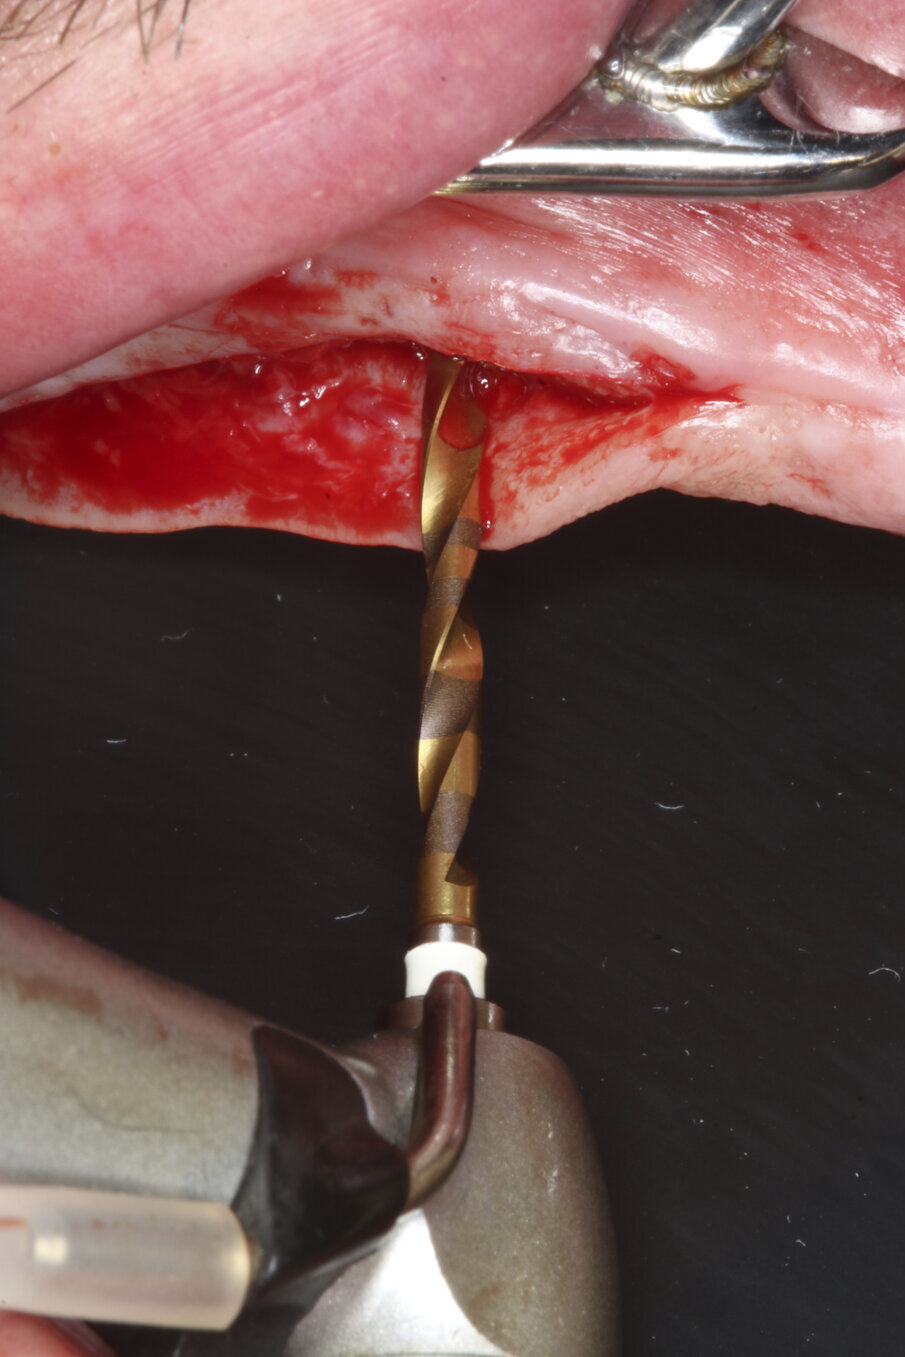

Prior to surgery, intra-oral scans of the edentulous upper jaw and dentate lower jaw were performed. The existing denture was used first as a surgical guide and then as a provisional prosthesis, after removing the palate (Fig. 4). Immediately after implant placement (Figs. 5–10), abutment position was registered with an intra-oral scan (Fig. 11). The provisional prosthesis was prepared fromthe existing denture (Figs. 12 & 13) and then the Atlantis BridgeBase was designed (Fig. 14).

Fig. 4: The existing denture was adapted to be used as a surgical guide and provisional prosthesis for immediate loading.

Fig. 5a–c: Implant bed preparation following the recommended drilling protocol for the planned implant using drill #1 (5a)...